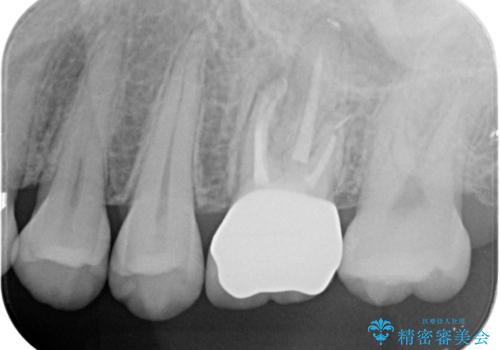

本来は歯茎をしっかりと下げる外科処置が適応となるケースでしたが、ご希望がなかったため最小限の侵襲に抑えて治療を行いました。

根の中を洗浄し、結果的に適合の良い被せ物をセットすることができました。

- 左上6:仮歯+ジルコニアクラウン/11,000円+121,000円 , 再根管治療(リトリートメント)+土台(ファイバーコア)/143,000円+22,000円費用は治療当時の料金となります